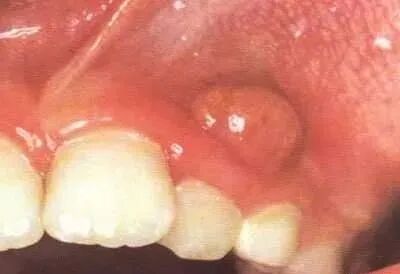

由于乳牙牙根的弯曲度较大,牙根又处于不断吸收中,根管治疗操作一定要小心谨慎,拔髓针不可插入根管过深。

拔髓针过深、过紧都很容易卡住,不仅难于拔除牙髓,还难于抽出,容易使拔髓针折断于根管中。